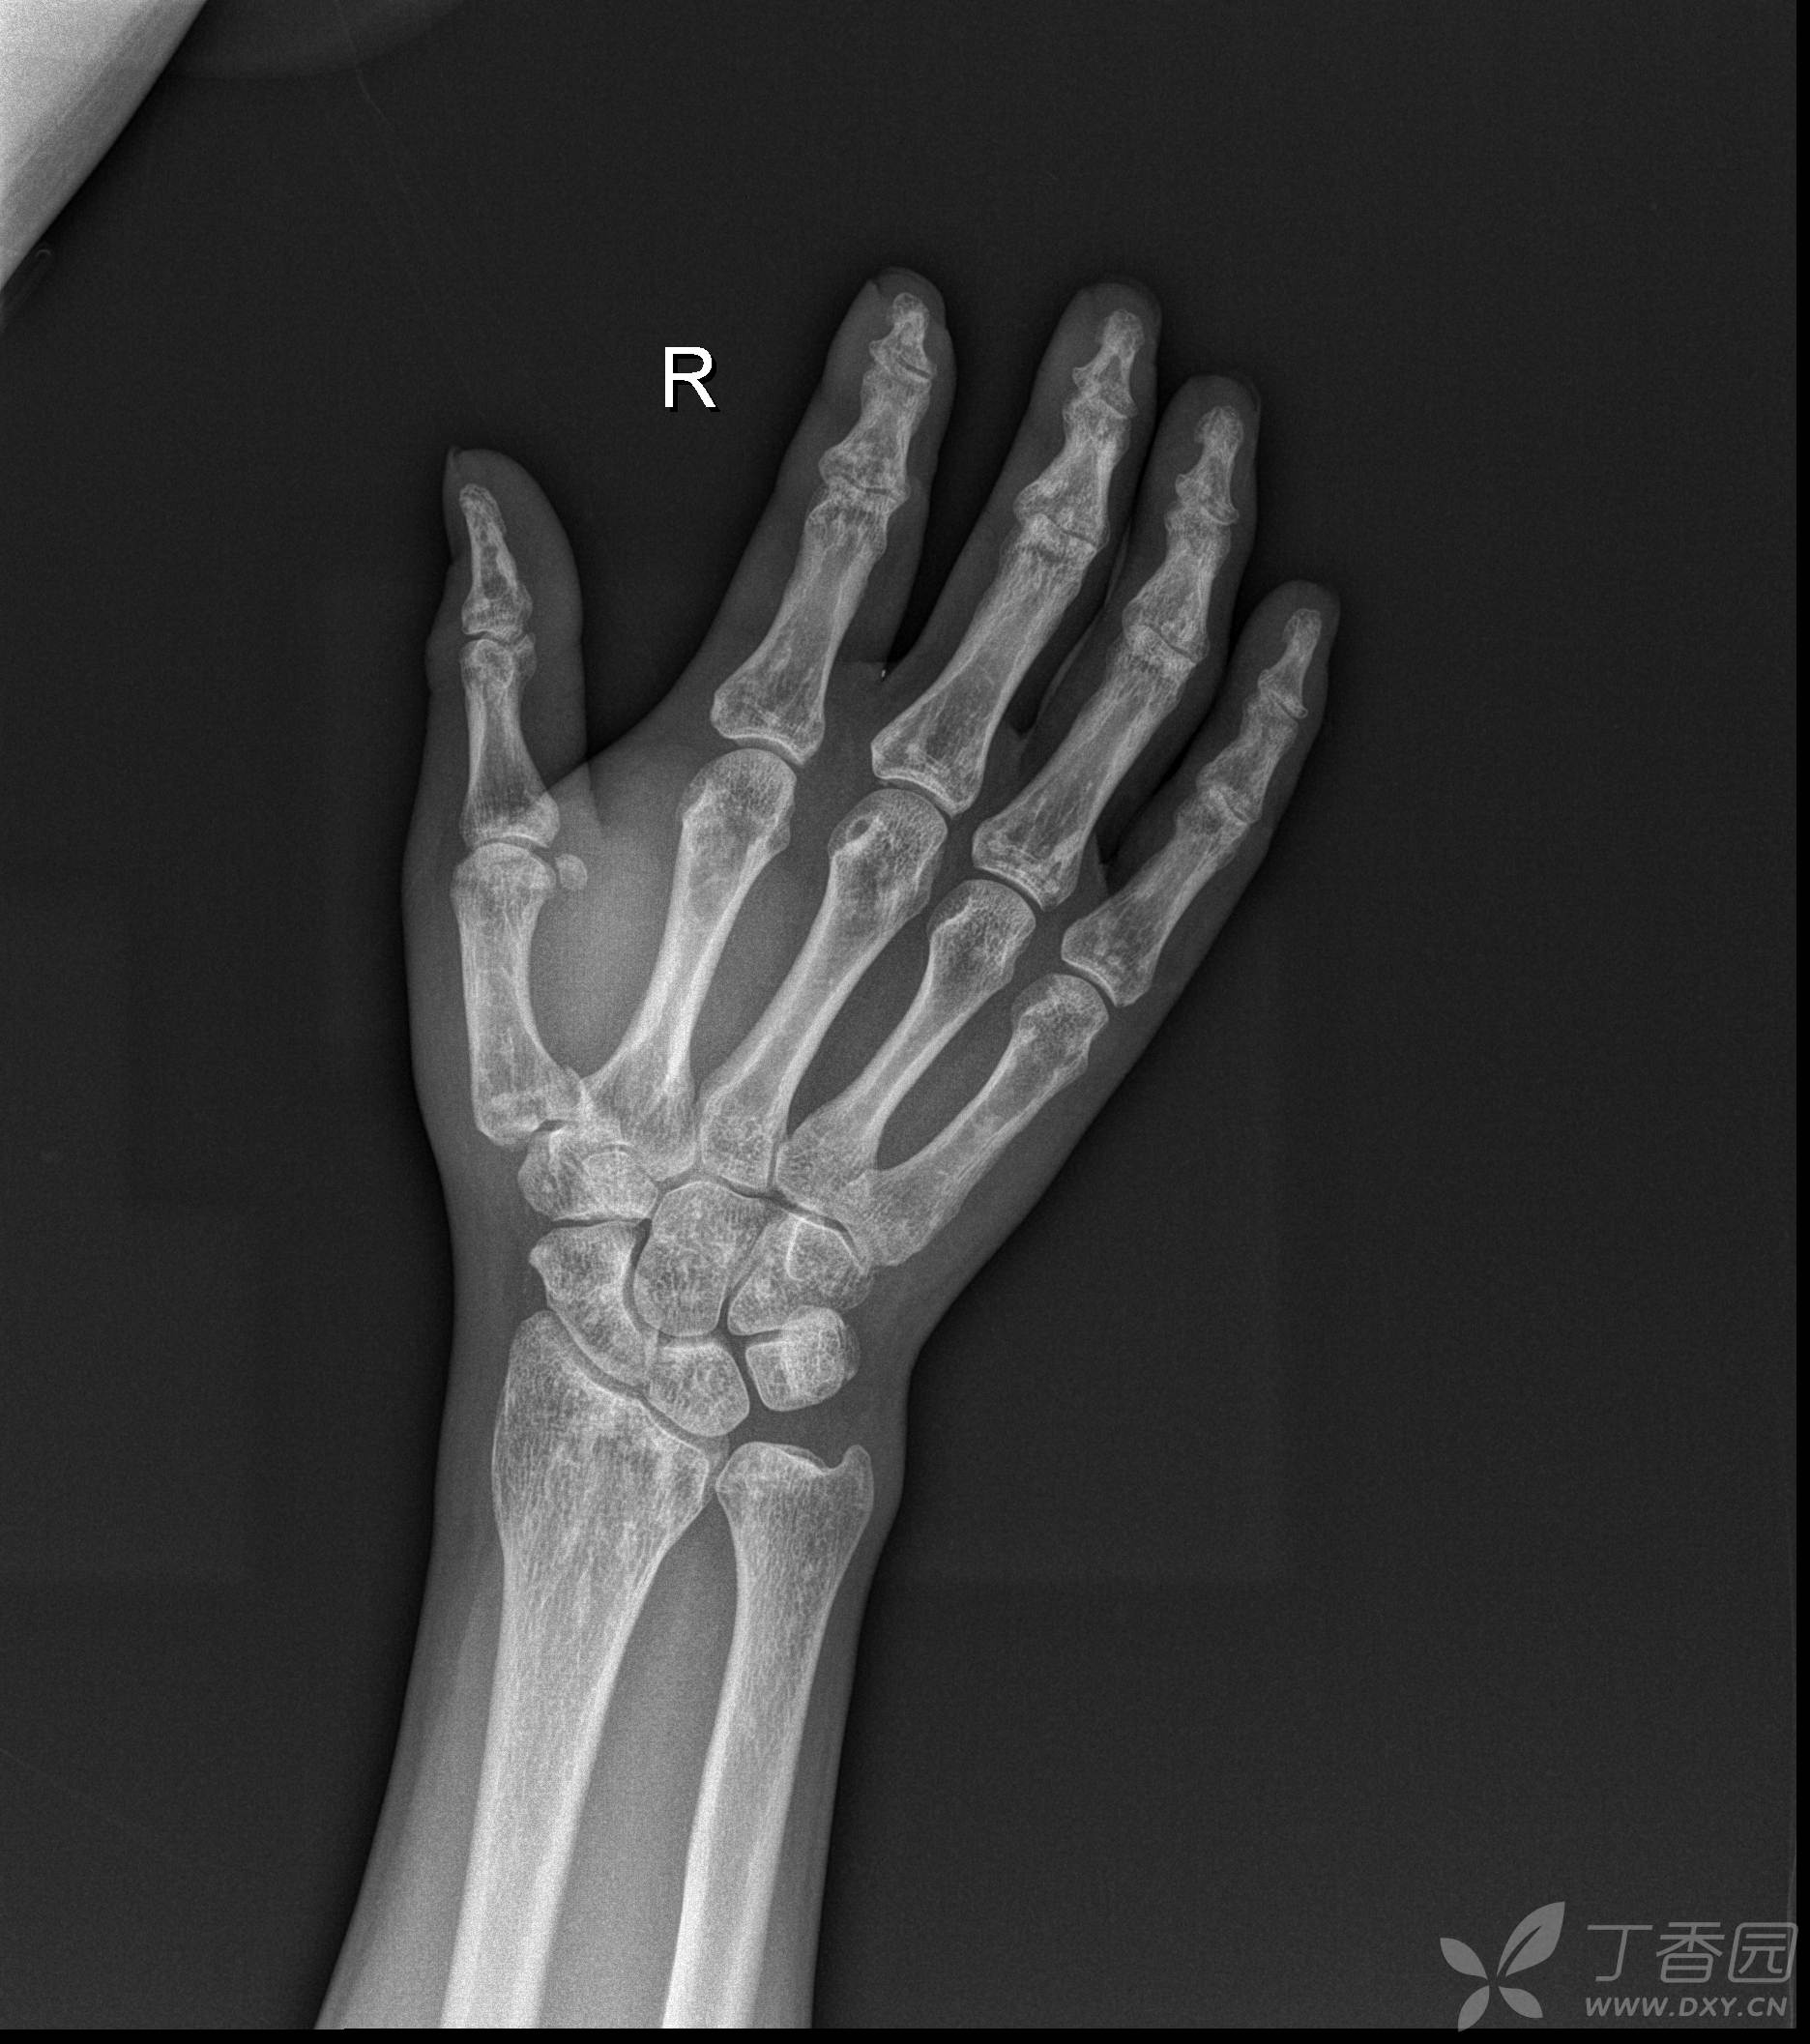

帮忙看看这个骨龄片,12周岁六个月的男孩子,骨龄片上显示骨龄多少岁?

请骨科专家看看骨龄片,168厘米的孩子还能否长高?万分感谢!

教你简单识别孩子的骨龄片